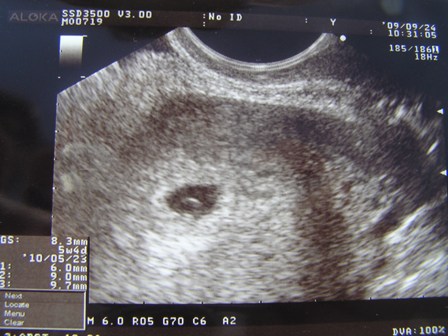

Remélem jól vagy, és biztosan hallani fogod a szívecskét 7-én.